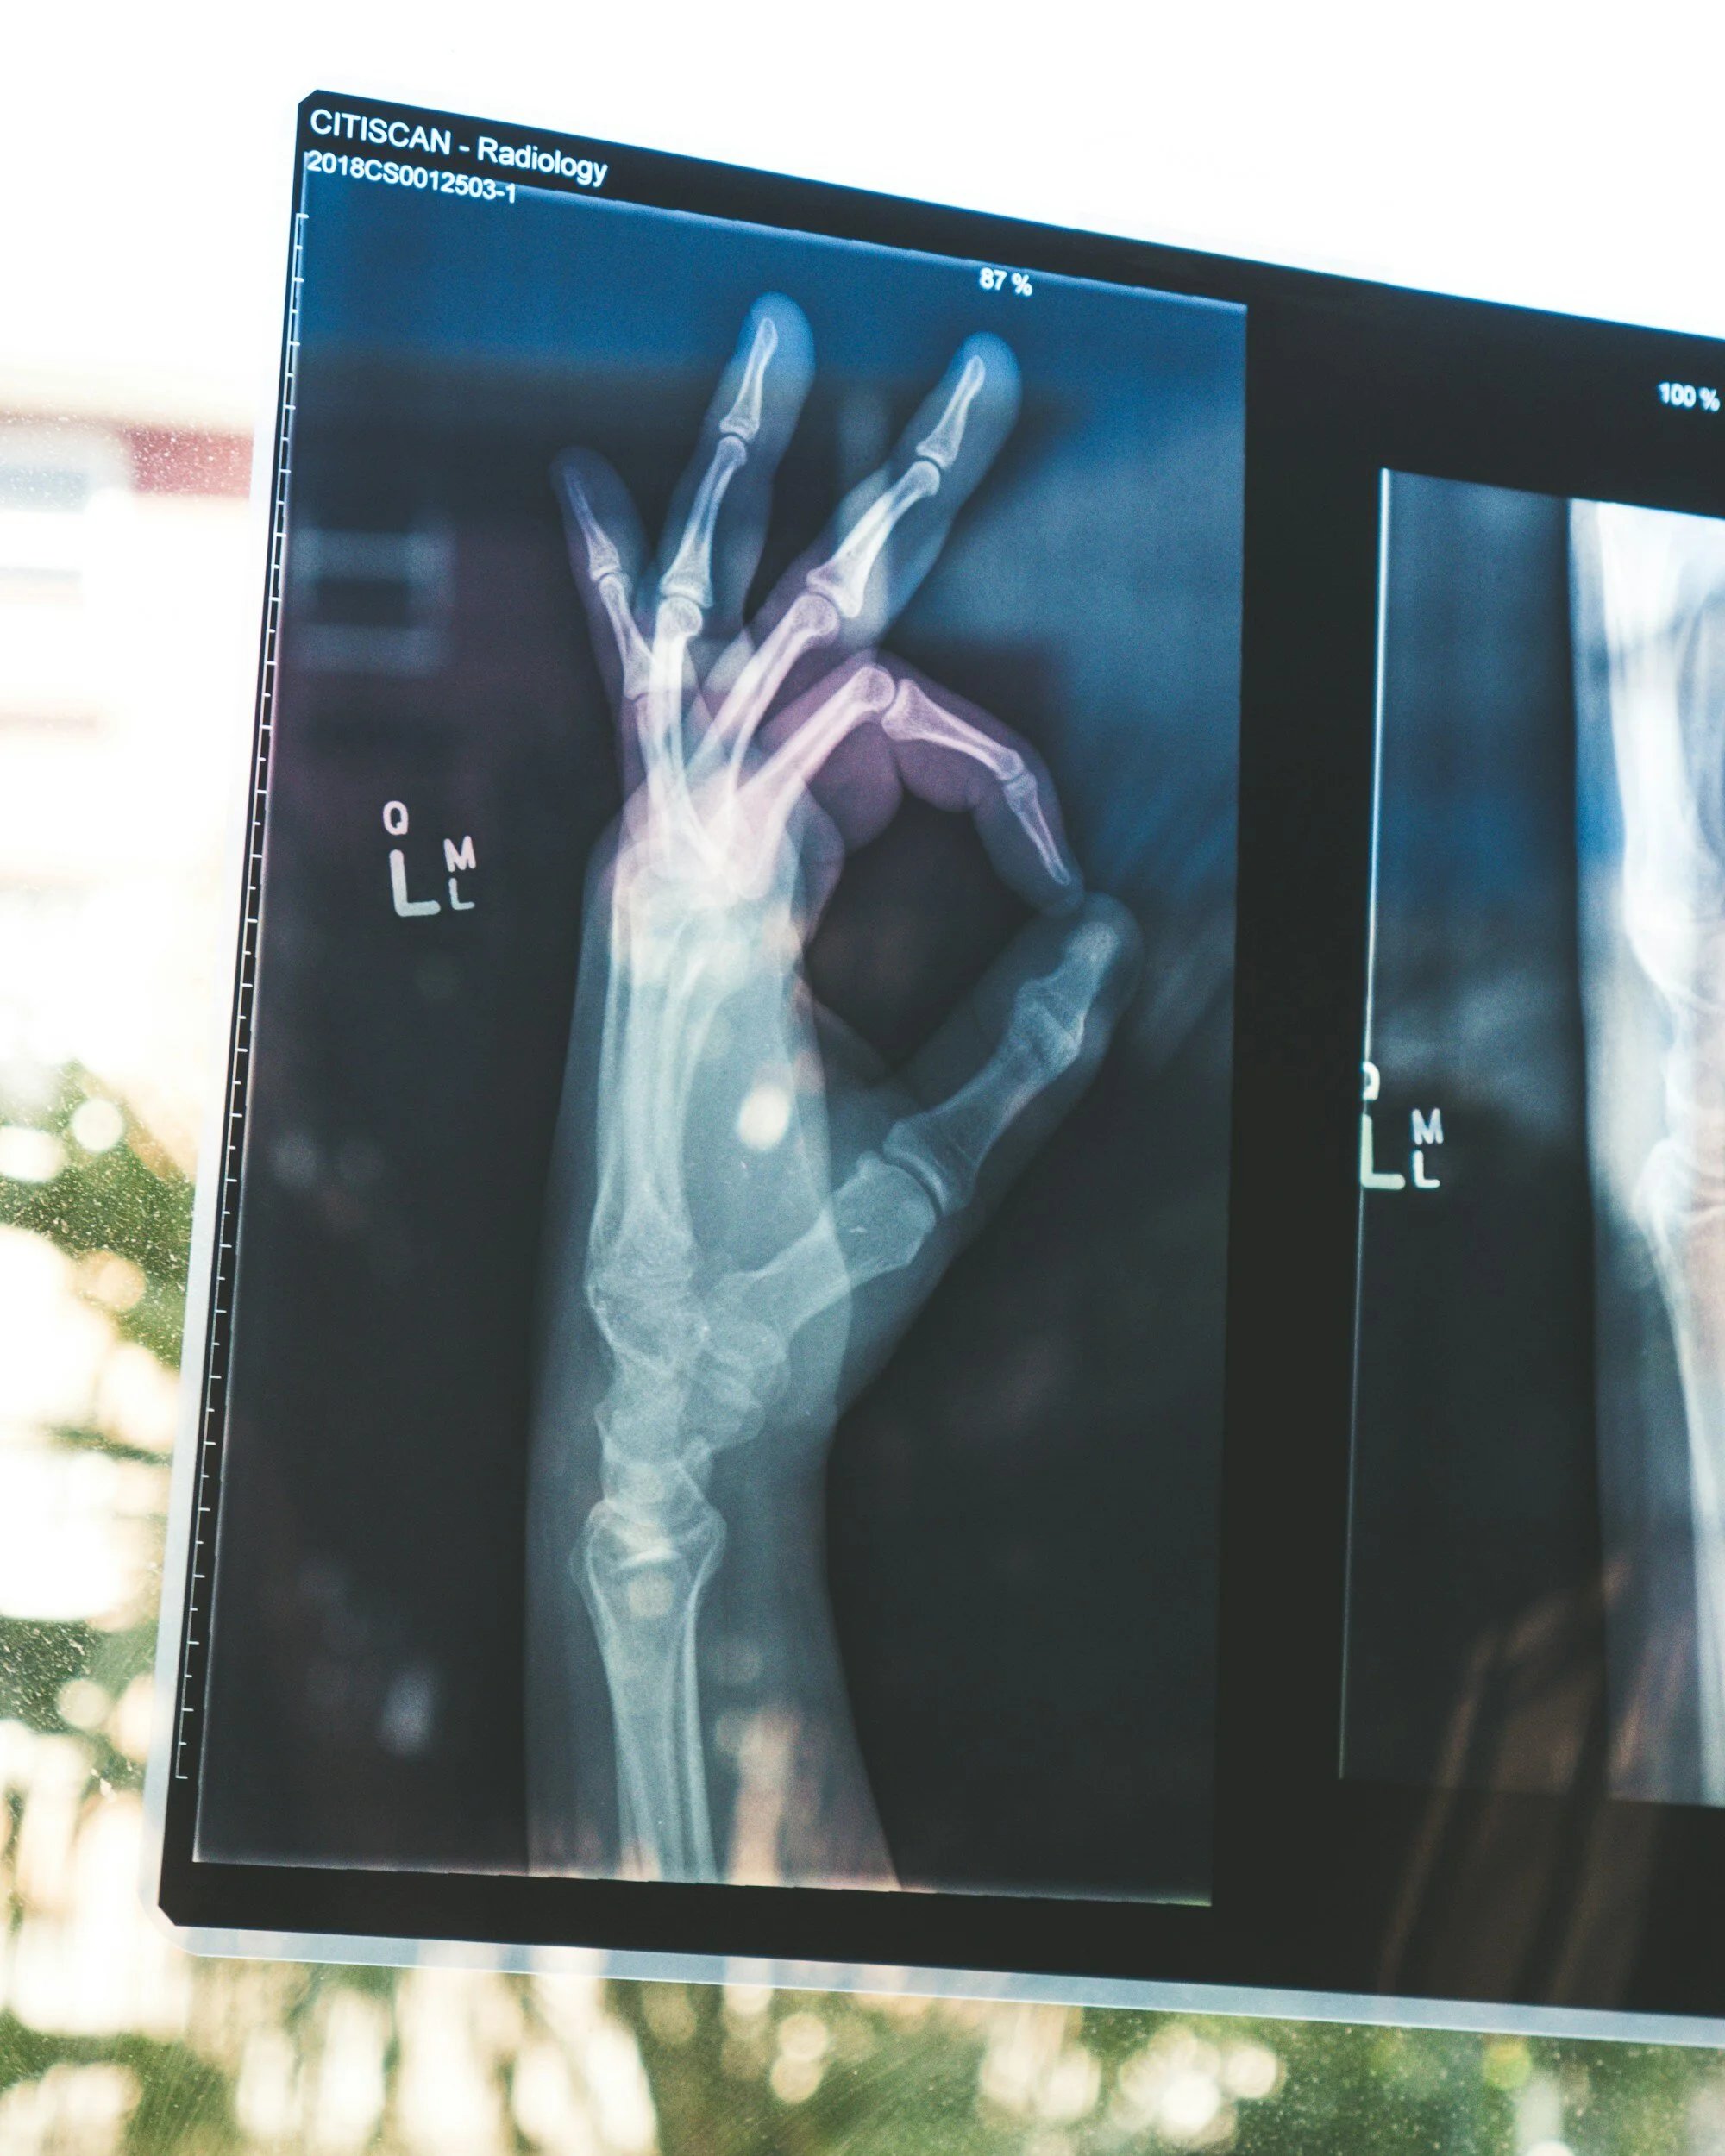

To get the most from your appointment, please ensure all relevant results are sent to us prior to your consultation. This includes X-rays, CT, ultrasound or MRI scans, and blood tests.